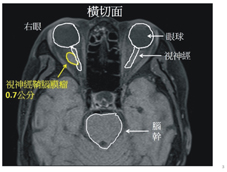

「看不見了!」 74歲的邱阿嬤陪孫子一起玩,小孫子要阿嬤讀繪本給他聽,卻又調皮的伸手遮住阿嬤的左眼。邱阿嬤大驚失色,因為眼前一片漆黑,沒有遮住的右眼竟然什麼都看不見。 驚駭莫名的邱阿嬤來到亞東醫院眼科部黃子倫醫師門診就醫,黃子倫醫師臨床推測阿嬤是視神經出了問題,經事後安排的磁振造影檢查,確診為一顆腦膜瘤(0.7cmX0.56cm)緊緊裹住阿嬤右眼視神經位於眼窩的一段,導致阿嬤視神經功能受到腫瘤壓迫影響(如:圖一)。

圖一、右眼視神經受到視神經鞘腦膜瘤瘤壓迫